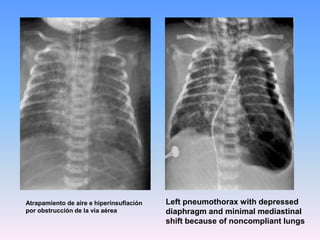

Left pneumothorax with depressed diaphragm and minimal mediastinal shift because of noncompliant lungsAtrapamiento de airee hiperinsuflaciónporobstrucciónde la via aérea